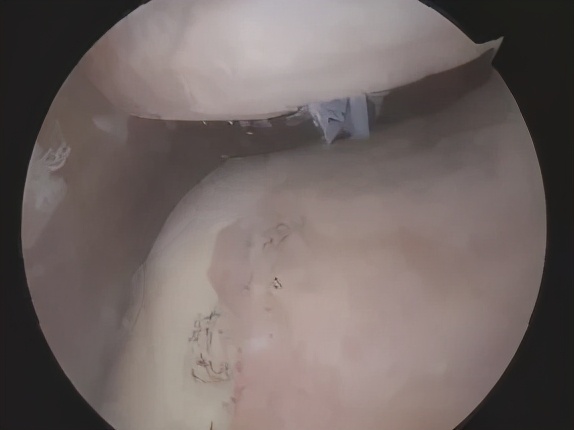

内侧半月板损伤

半月板是膝关节内一个“垫片”结构,起到缓冲、稳定关节的重要作用。因此,一旦内侧半月板出现撕裂,就会出现4号位和偏内后侧的长期疼痛。

最常见于长期需要下蹲的职业,如木工、水电工、泥水匠等,年轻人多是在剧烈运动,如踢足球、打篮球等时,膝关节屈曲高速旋转,从而造成内侧半月板损伤。如果半月板损伤严重,时间长了可能需要手术切除。切除后,骨头跟骨头硬碰硬,就像光脚走路似的,软骨磨损也会加快。所以,大家一定要注意保养好半月板!